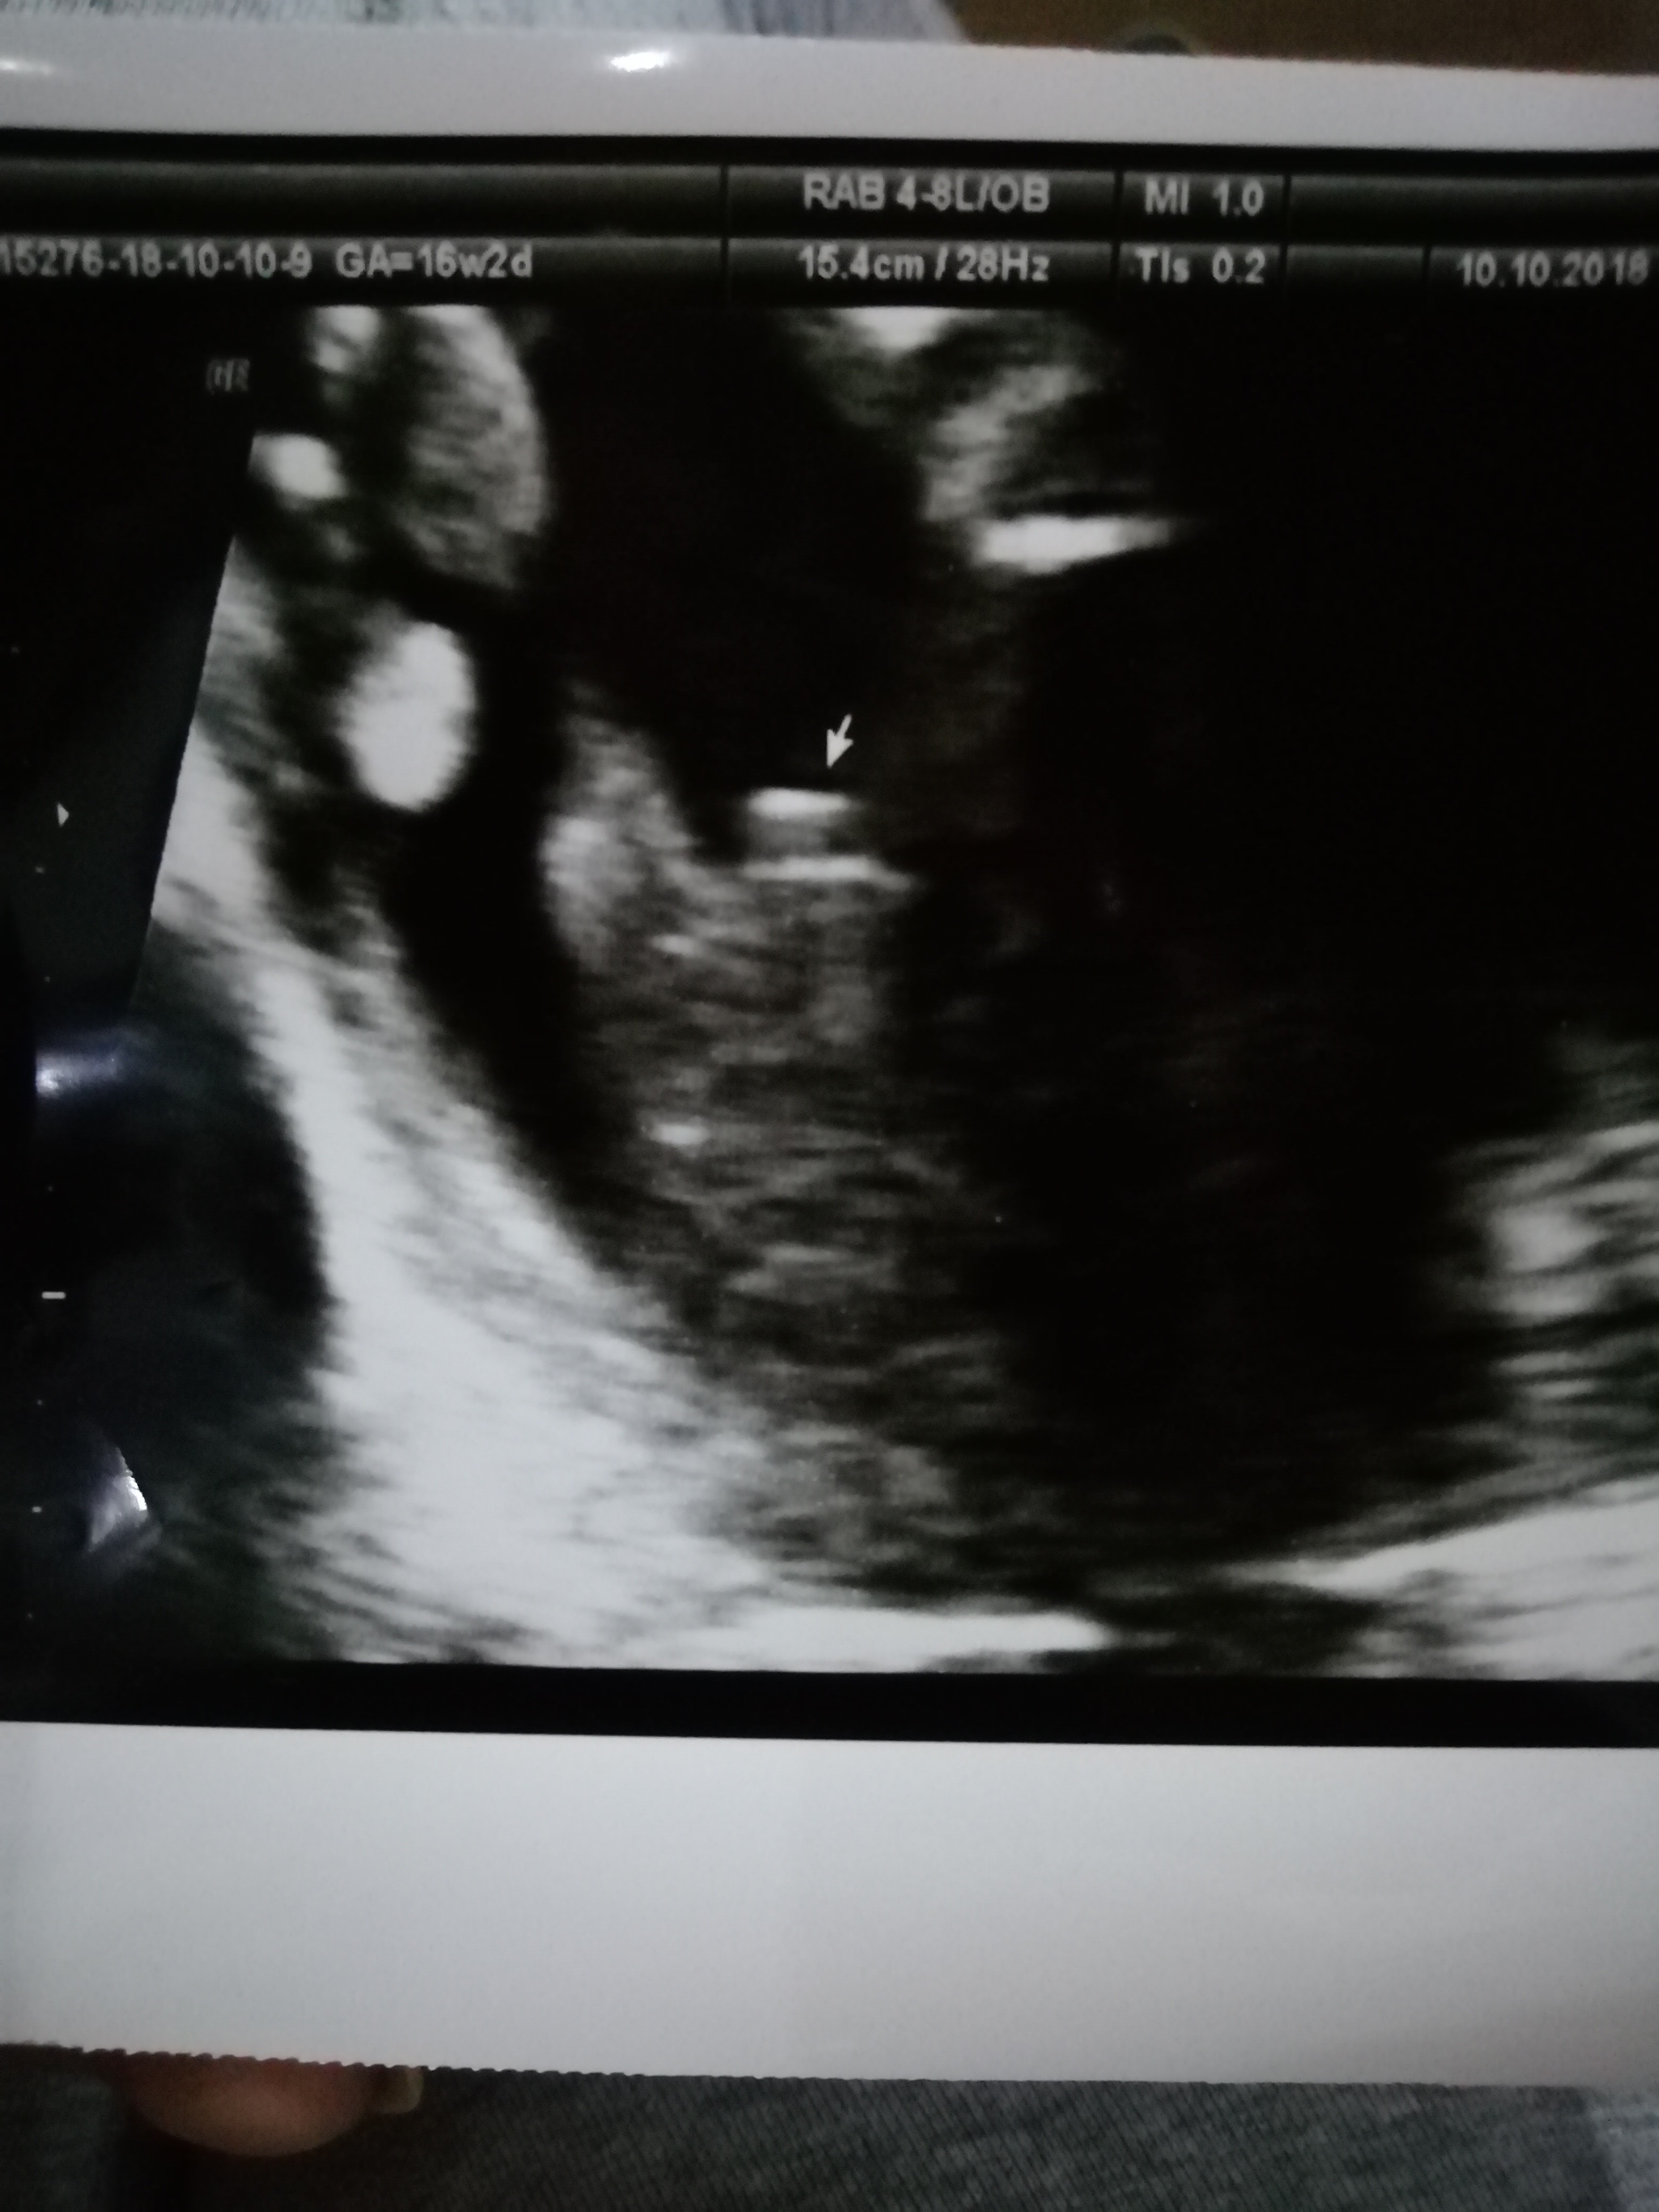

Cześć dziewczyny proszę was o ocenę zdjęcia usg... Miesiąc temu zapowiedzieli mi syna a 4 grudnia na połówkowym ze córka... Trochę mam mętlik w głowie 😞

A tutaj po tym zdjęciu, co byś powiedziała ? :)

Sysia obstawialabym chlopaka na potty shot cos odstaje..mojej corce w tym tyg ciazy nic nie odstawalo.

Klaudia przykro mi ale na Twoich zdjeciach nie widze nuba.

Justyna czy to platna opinia? Jesli tak to nie bierz jej pod uwage...wiem ze robia to na odwal..niby coa widac na Twoim zdjeciu ale jest ono mega slabe..